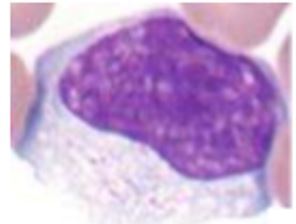

Q

wtf is that

A

Un petit lymphocyte waouh

cause Noyau prend presque tout la cellule et est full sombre